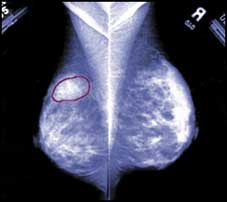

السبب غير معروف.. ويكثر عند النساء البدينات!!

وجود إفرازات من الحلمة حمراء أو بيضاء أو صفراء أحد أعراض سرطان الثدي!!

السبب الرئيسي للإصابة بسرطان الثدي غير معروف، ولكن الإحصاءات تثبت أو واحدة من كل تسع سيدات «في أمريكا» معرضة للإصابة مرة واحدة خلال حياتهن كما بينت ا.........